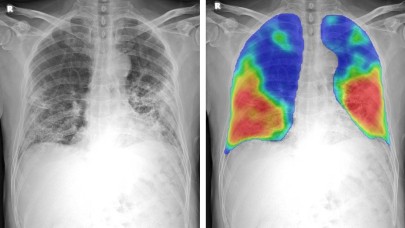

COVID-19'un etkileri röntgenlerde çıkmaya başlayacak!